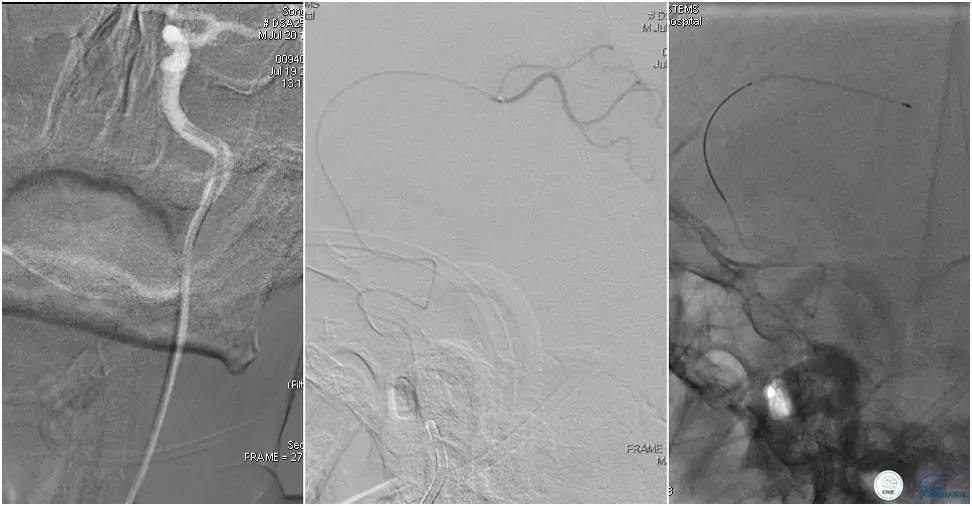

6F Envoy置于颈内动脉C3段,选用Solitaire-FR 4*20mm支架释放于右侧大脑前动脉,完全覆盖血栓。

6F Envoy置于左侧颈内动脉C3段,选用Solitaire-FR 4*20mm支架释放于右侧大脑前动脉取栓1次,血流达TICI 2b。

Solitaire-FR 4*20mm支架释放于左侧大脑前动脉取栓1次,取出少许血栓重复造影左侧大脑前动脉胼周动脉开口后,右侧大脑前动脉A2段以远未显影,考虑栓子逃逸。

选用Solitaire-FR 4*20mm支架分别于右侧大脑前动脉A2-A3段,左侧胼周动脉,右侧胼周动脉取栓3次。

双侧大脑前动脉完全显影,TICI 3级,TOR 261min。